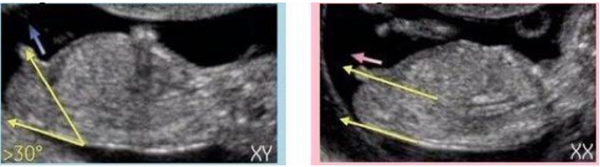

NT单子上会有宝宝的图片,我们在图片上可以看到具有性征的一些身体特点,男孩的特征点与身体呈45度角,还多一些,而女孩儿的特征点几乎和躯体平行。还有就是如果是男宝宝,屁股位置会微微上翘,后背脊柱成圆弧状,因为要留空间发育前列腺,相反,女宝宝后背脊柱就相对就平一些。

(NT胎儿男女对照图)